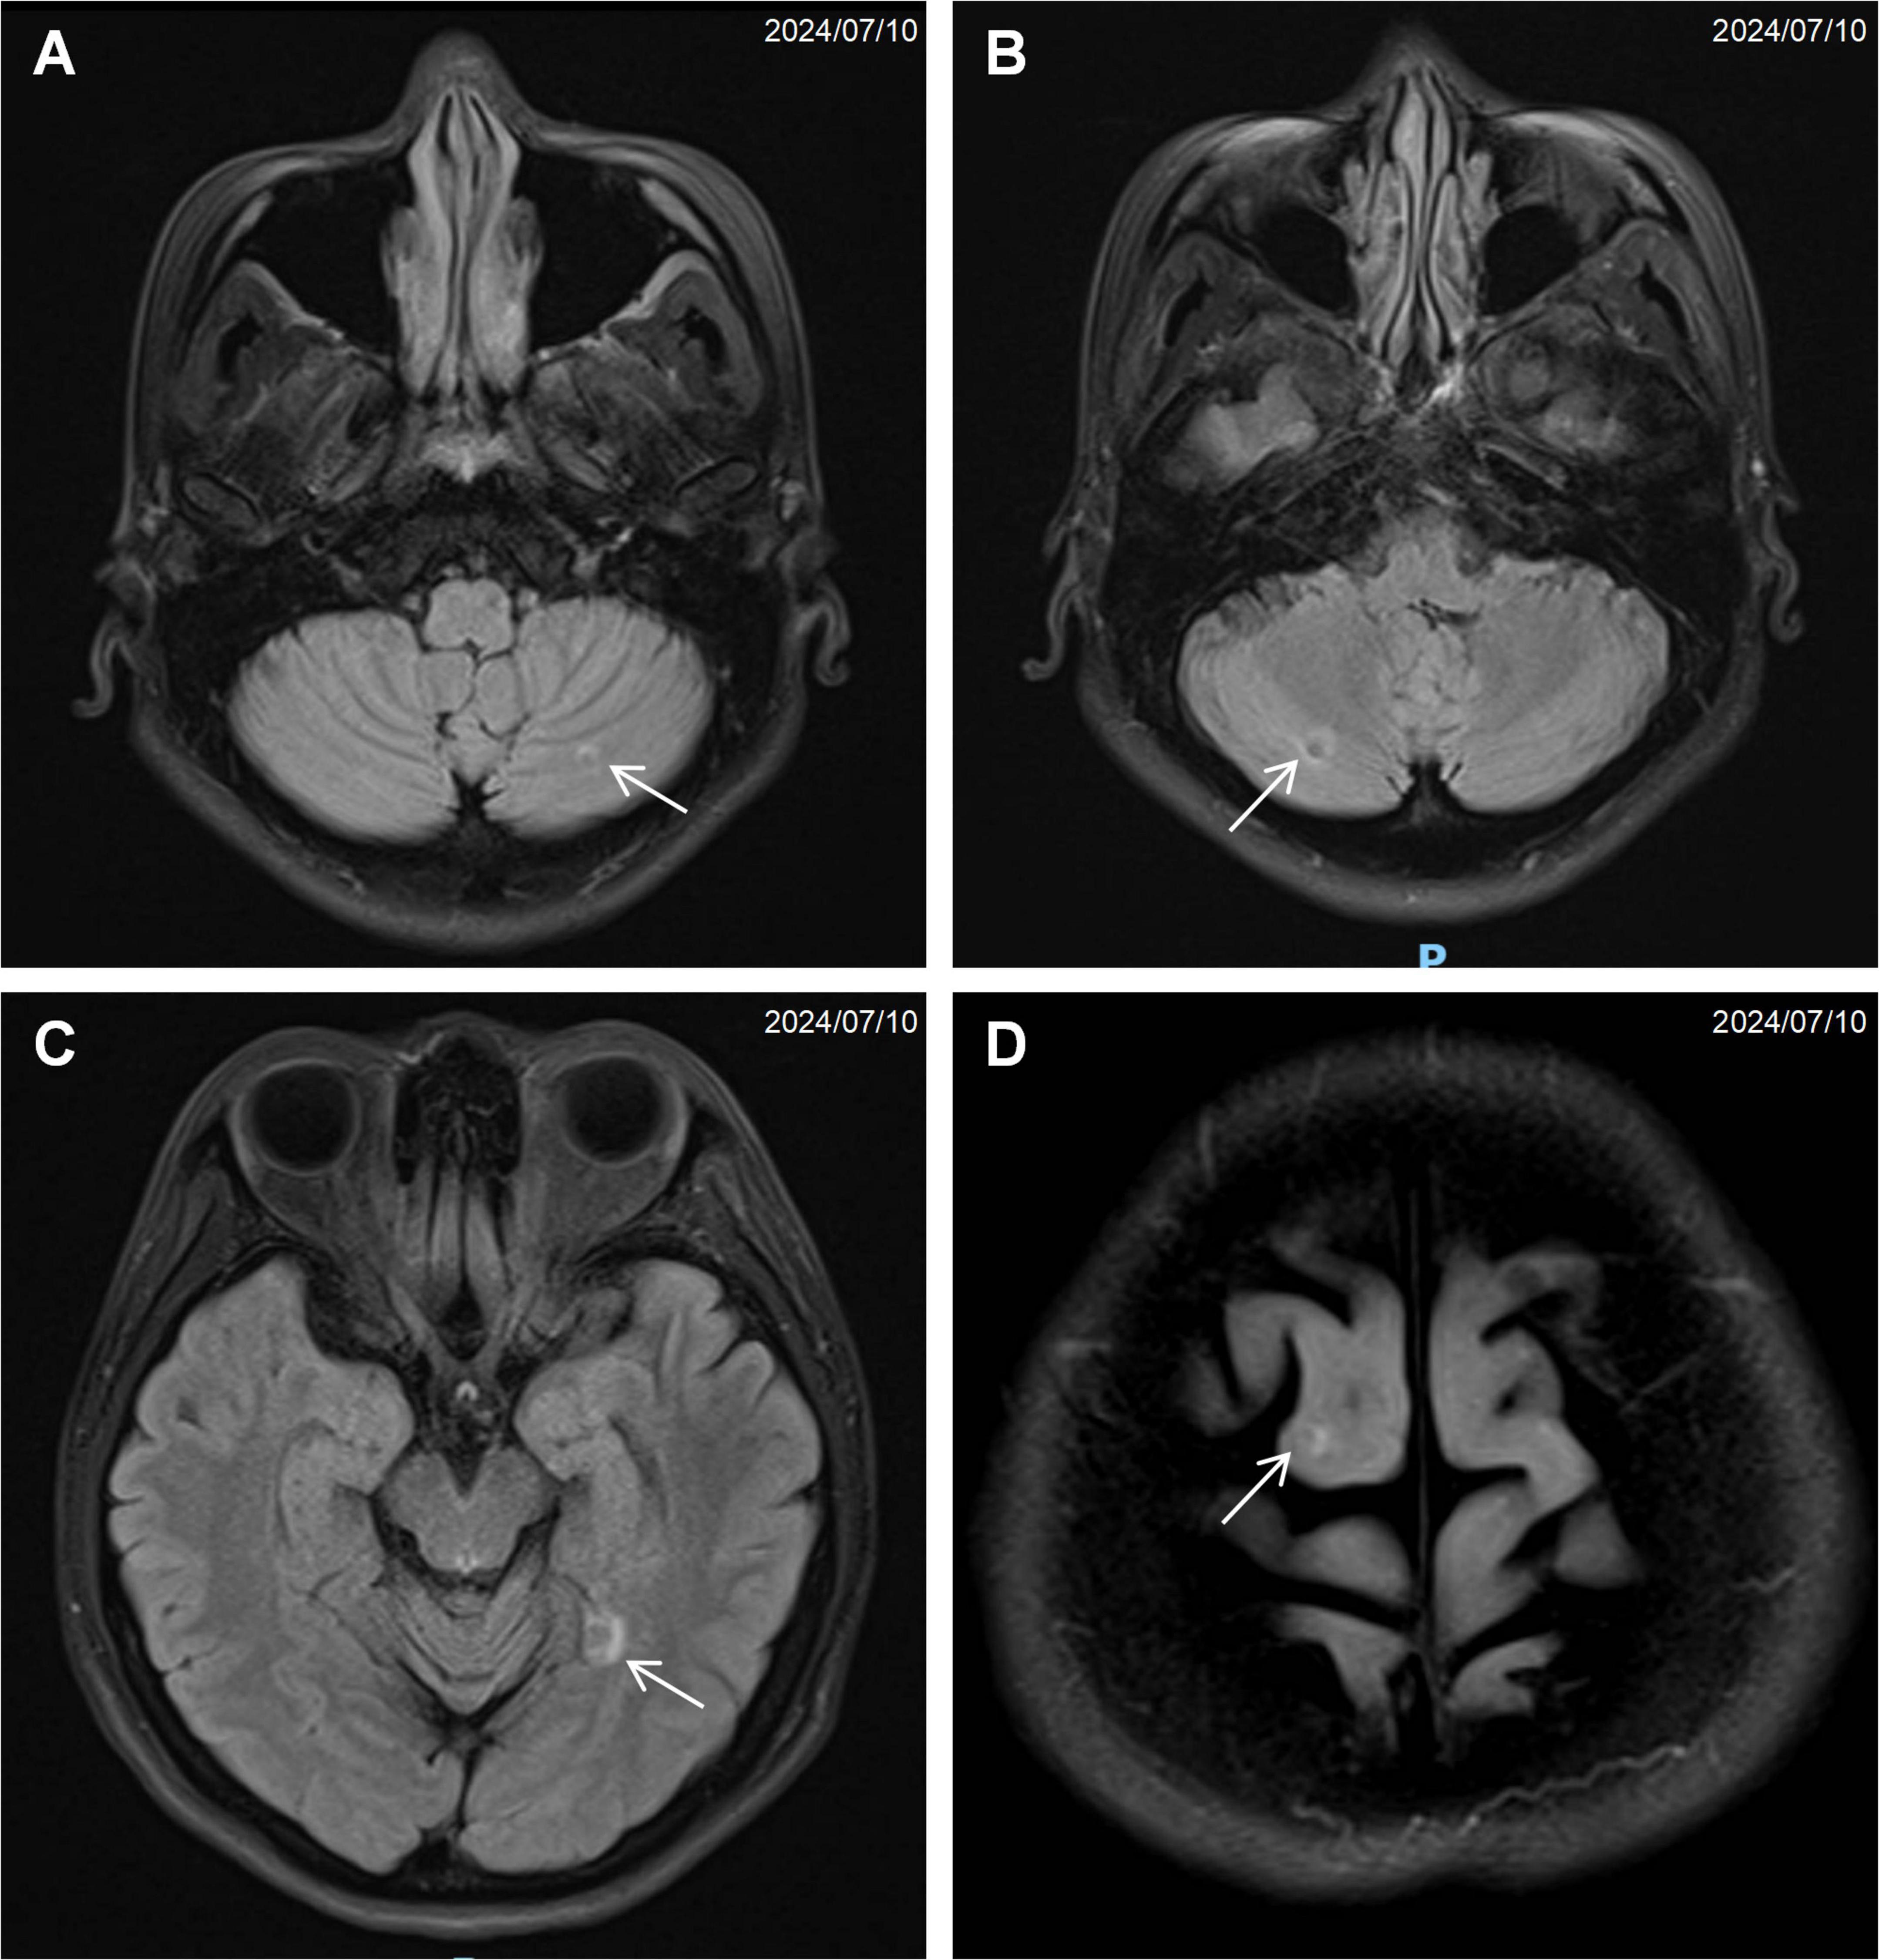

Computed tomography of the chest, abdomen, and pelvis revealed multifocal lesions involving the left lung, pancreas, appendix, and bilateral adnexa (Figure 1). A solid left upper lobe mass (40 × 34 × 46 mm) demonstrated heterogeneous enhancement with bronchial cutoff and pleural indentation. Pancreatic lesions included hypodense masses in the uncinate process (20 mm × 18 mm; progressive enhancement) and tail (28 mm × 22 mm; heterogeneous enhancement). An appendiceal nodule (13 mm × 9 mm) showed uniform enhancement with ileocecal lymphadenopathy. Complex cystic-solid adnexal lesions were observed, largest in the left ovary (55 × 52 × 52 mm). Differential diagnosis included primary lung adenocarcinoma and NET, with additional lesions noted in the thyroid, left breast, and T8/L5 vertebrae. Magnetic resonance imaging (MRI) of the chest and abdomen confirmed multi-organ involvement (left lung, pancreas, bilateral adnexa) with iso- to hyperintense signals. Vertebral MRI demonstrated a T8 nodule (14 mm × 8 mm) with long T1/T2 signals. Cranial MRI showed normal pituitary architecture but abnormal foci in cerebellar hemispheres, left temporal lobe, and right frontal lobe, the largest (4 mm) in the left frontal lobe (Figure 2). Thyroid ultrasound revealed C-TIRADS 4A nodules, with the largest measuring 29 × 22 × 15 mm and showing heterogeneous enhancement on contrast-enhanced ultrasound.

FIGURE 2

Magnetic resonance imaging (MRI) of the brain showing multiple small nodular signal abnormalities: (A) left cerebellar hemisphere (arrow), (B) right cerebellar hemisphere (arrow), (C) left temporal lobe (arrow), (D) right frontal lobe (arrow).